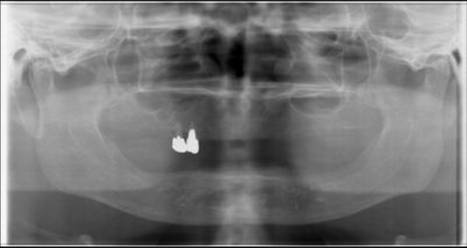

顎堤異常もないとてもきれいなパノラマ写真です。

右上の3・4がだめになって来院されました。